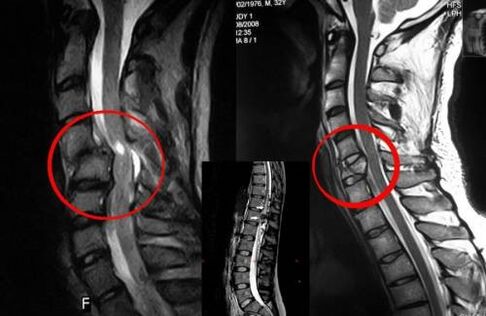

Diagnosticare

Diagnosticul de osteocondroză include un examen medical al coloanei vertebrale

Osteocondroza vertebrală necesită consultarea în timp util a unui medic care va ajuta la refacerea spatelui deteriorat. Echipamentele moderne fac posibilă efectuarea unui diagnostic în stadiile incipiente de dezvoltare. În caz de patologie, contactați un neurolog sau ortoped. În primul rând, se efectuează o examinare a coloanei vertebrale rănite și se face un istoric medical, apoi se prescriu metode de diagnostic de laborator și instrumentale care identifică osteocondroza:

• radiografie;

• mielografie;

• examen neurologic;

• CT și RMN;

• rezonanță magnetică nucleară.

Compresia măduvei spinării - o indicație pentru intervenție chirurgicală

Când este necesară intervenția chirurgicală?

Dacă osteocondroza cronică a coloanei vertebrale s-a dezvoltat la adulți și terapia conservatoare nu ajută, atunci se recurge la măsuri terapeutice radicale. Intervenția chirurgicală este, de asemenea, necesară în următoarele cazuri:

• subluxație vertebrală;

• hernie;

• compresie acută a măduvei spinării;

• deformarea coloanei vertebrale.